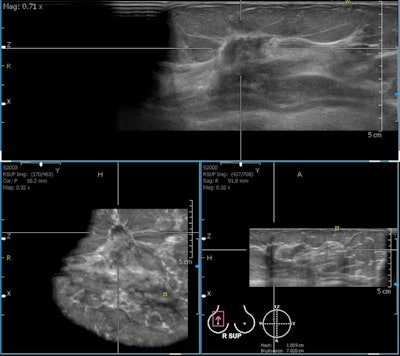

This technology is based on computer generation of a 3D imaging dataset obtained from many parallel 2D images. It offers a different approach with a variety of benefits, he said. Images are obtained by the sonographer in a standardized fashion; whole breast datasets can be reviewed at any time after the examination, which reduces operator dependence, and image fusion with MRI, for instance, is possible.

Automated breast ultrasound is indicated in screening patients in whom incidental cancers would be expected, according to Fuchsjäger. Scientific studies show automated breast ultrasound's highest value is for high-risk screening populations -- i.e., patients younger than 50, with dense breast tissue, a personal history of breast cancer, or a genetic risk.

"Automated breast ultrasound would fit perfectly as a complement to screening mammography in women with heterogeneous dense or very dense breast tissue (BI-RADS composition 3 or 4)," he stated. "It is not intended to replace handheld breast ultrasound, which is the method of choice for evaluation for suspicious lesions, preoperative staging, axillary lymph nodes assessment, as well as ultrasound-guided breast interventions."

However, handheld ultrasound is a highly operator- and experience-dependent modality. Real-time adjustments (gain, focal zones, dynamic range, pressure, etc.) are necessary for good results, and abnormalities have to be recognized at examination, otherwise they are missed. With automated breast ultrasound, on the other hand, there are standardized views (like in mammography) for better reproducibility. Acquisition is separated from interpretation, and second reading, like with screening mammography, is an option, he continued.

Limitations include lower ultrasound frequency than for handheld devices, no Doppler analysis or elastography imaging, difficulty in scanning the axillary region, and the relatively large amount of data (0.7-1.0 GB per examination). Artifacts can be an issue due to the bigger transducer (15 cm).